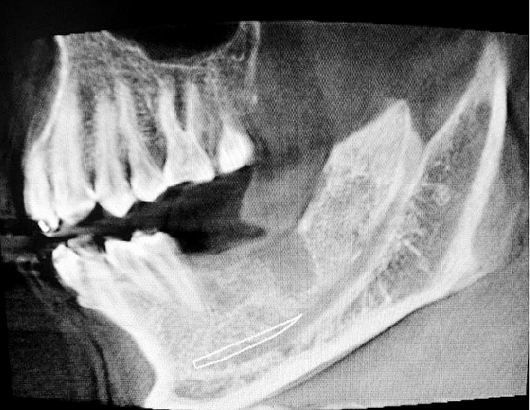

ct定位

額外牙拔除

好大的額外牙